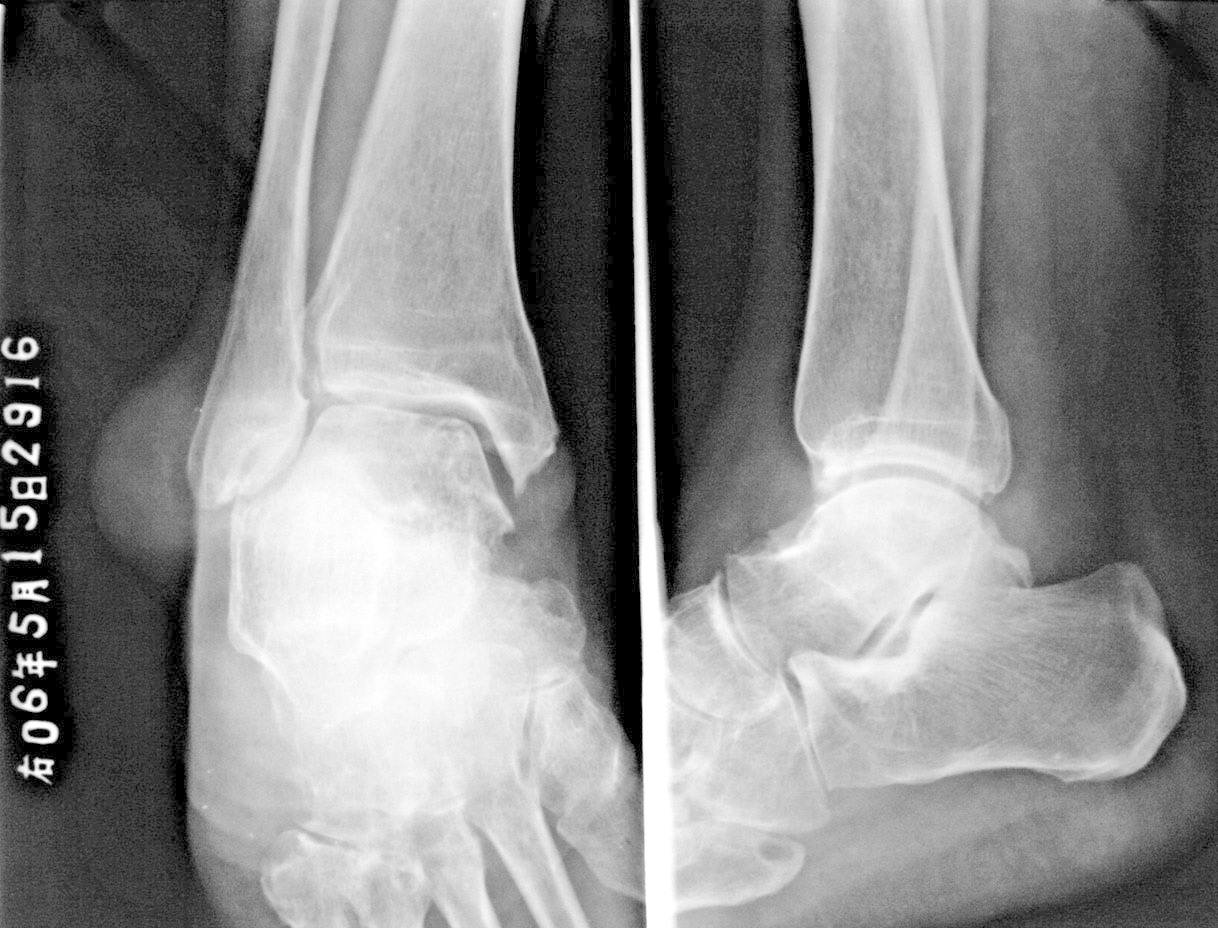

痛风,外踝之软组织肿物?

痛风,外踝软组织肿块影呢

痛风所致关节病变,软组织肿块为通风形成的皮下结节

支持痛风---穿凿状破坏,软组织肿块,痛风石形成。

穿凿样骨质破坏及及足、外踝痛风结节形成符合痛风性关节炎。

痛风,外踝之软组织肿物?经典!

痛风伴蜕变.踝关节处应该是软组织肿物吧.好象没有看到骨质吸收和压迫改变

尿酸高,该患者患病已经近十年,双手及双足均可见多发明显病变。